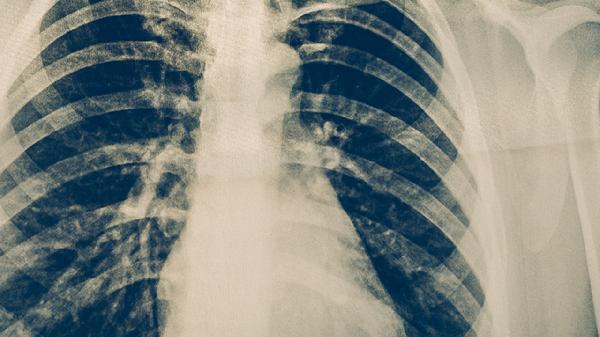

肺結(jié)核的治療方法主要有化學(xué)藥物治療、手術(shù)治療、營養(yǎng)支持治療、心理干預(yù)和隔離防護(hù)措施。肺結(jié)核是由結(jié)核分枝桿菌感染引起的慢性傳染病,需在醫(yī)生指導(dǎo)下進(jìn)行規(guī)范治療。

肺結(jié)核患者在治療期間應(yīng)注意休息,避免過度勞累。保持規(guī)律作息,戒煙限酒。適當(dāng)進(jìn)行散步、太極拳等溫和運動,增強體質(zhì)。定期復(fù)查胸部X線或CT,監(jiān)測病灶變化。嚴(yán)格遵醫(yī)囑用藥,不可自行增減藥量或停藥。注意個人衛(wèi)生,勤洗手,避免交叉感染。飲食宜清淡易消化,多飲水促進(jìn)痰液排出。如出現(xiàn)藥物不良反應(yīng)或癥狀加重,應(yīng)及時就醫(yī)調(diào)整治療方案。